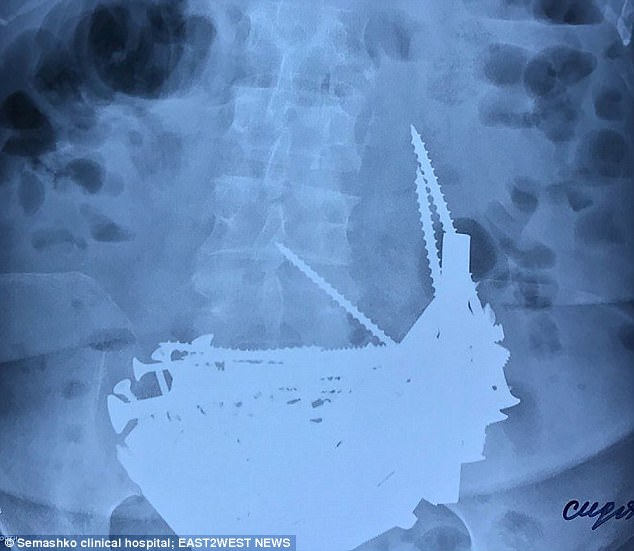

Mangsa mengadu mengalami suhu badan yang tinggi, namun kakitangan hospital amat terkejut apabila mereka menemukan punca penyakit warga emas itu menerusi sinaran X (X-ray).

Memetik laporan Daily Mail, pakar bedah menjumpai lebih 152 objek asing di dalam badannya.

Antara objek itu adalah paku panjang, skru bersaiz besar, bolt dan penghenti pintu serta cebisan besi sepanjang enam inci.